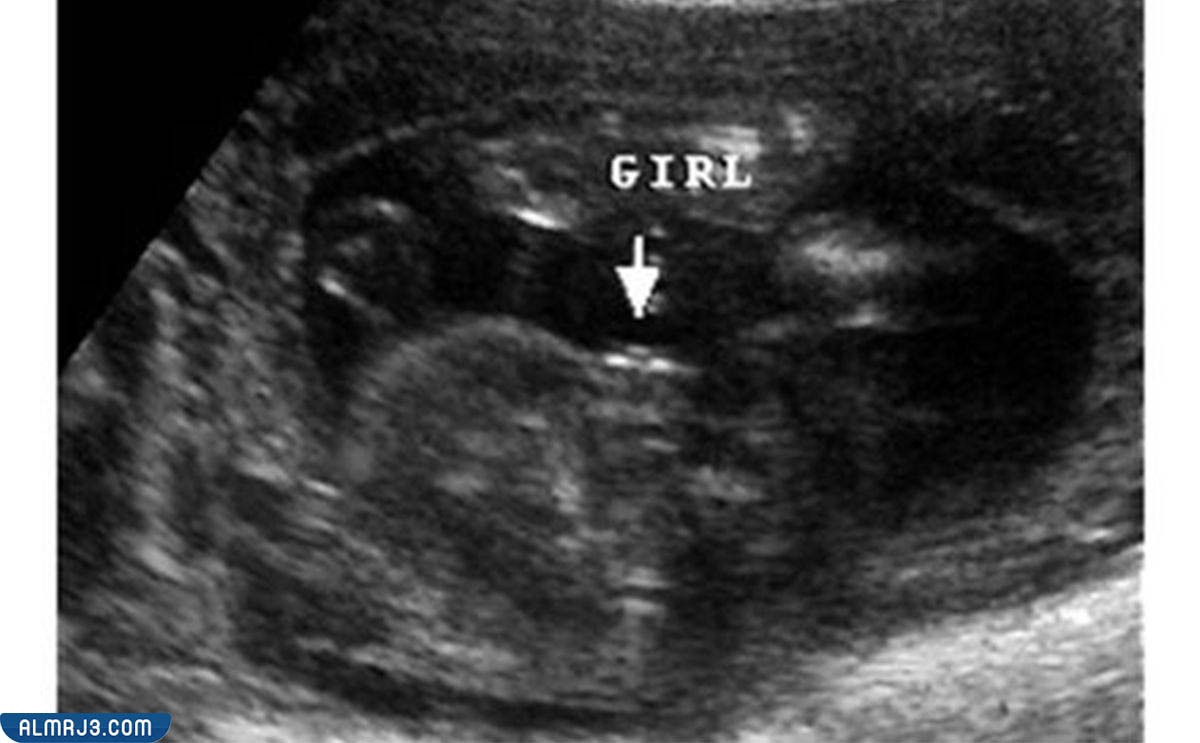

الفرق بين سونار البنت والولد في الشهر الرابع

تساعد أجهزة السونار في توضيح عدد الأجنة الموجود داخل الرحم، كما يساعد في توضيح نوع الجنين بمنتهى السهولة ومع اكتمال ووضوح الأعضاء التناسلية، ويظهر الفرق بين سونار البنت والولد في الآتي:

- تمتلك الجنين الأنثى العضو الأنثوي وذلك إلى جانب الشفرتين، فتظهر في السونار وكأنها ثلاثة خطوط بيضاء.

شكل الجنين داخل السونار في الشهر الرابع

يختلف شكل الجنين الذكر في السونار عن شكل الجنين الأنثى، ويظهر ذلك الأمر بطريقة واضحة في الآتي:[2]

شكل الجنين الأنثى

تمتلك الأنثى ثلاثة خطوط بيضاء لتعبر عن العضو الأنثوي والشفرتين.